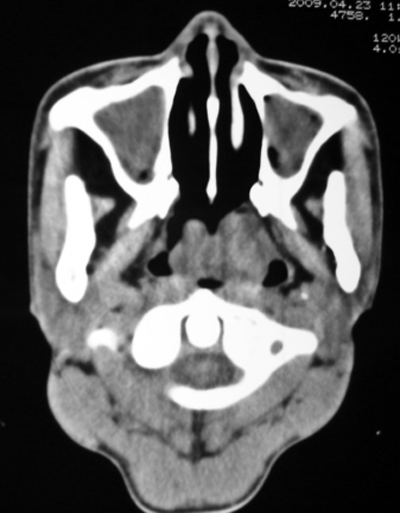

以下是引用bmw011在2009-4-23 13:23:00的发言:[br]考虑鼻息肉,上颌窦、筛窦炎

以下是引用syfszcw在2009-4-23 13:21:00的发言:[br]双侧上颌窦 筛窦慢性炎症,鼻息肉 会厌ca[br][br][本贴已被 syfszcw 于 2009-4-23 13:36:46 修改过]

以下是引用随光逐影在2009-4-23 19:35:00的发言:[br]1)鼻咽、口咽、左侧鼻腔及右侧鼻后孔处新生物,考虑息肉可能性大。2)双侧上颌窦及双侧筛窦炎症,不排除双侧上颌窦内息肉可能。